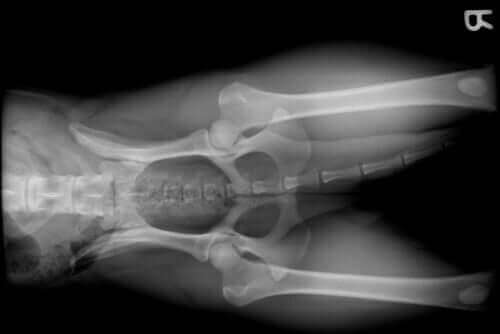

반려견에게 흔히 나타나는 질환 중 하나가 바로 관절 질환이다. 반려견이 다리를 절거나 급작스러운 통증을 호소하기 전까지는 보호자가 발병 여부를 알기 어렵다.

- 견종: 저먼셰퍼드 같은 특정 견종은 고관절이형성증, 골든레트리버, 로트바일러와 도베르만 등의 대형 견종은 어깨와 팔꿈치 이형성증에 걸리기 쉽다

- 골절: 관절 관련 골절 문제

- 전방 십자인대 부상: 과도한 운동, 과로 또는 반려견의 작은 체구 때문에 전방 십자인대 부상이 발생하면 심각한 관절 문제가 생길 수 있다